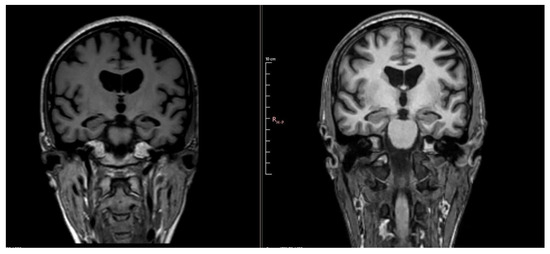

| Year 3 (1 year ago) | MMSE 9/30, MoCA 4/30 | Tau ↑ 877 pg/mL; p-Tau ↑ 63.6 pg/mL; Aβ42 ↓ 0.94 | Hippocampal atrophy (MTA score 2); parietal atrophy (Koedam 2); severe corpus callosum thinning with splenium demyelination (T2/FLAIR hyperintensity, T1 hypointensity) | Severe cognitive disorder requiring permanent care; anxiety and depression prominent |

| Year 4 (Current) | Severe impairment, no formal testing | Not repeated | Global progression of atrophy; no new lesions | Severe apathy, hypersomnia, total dependence, high wandering risk |